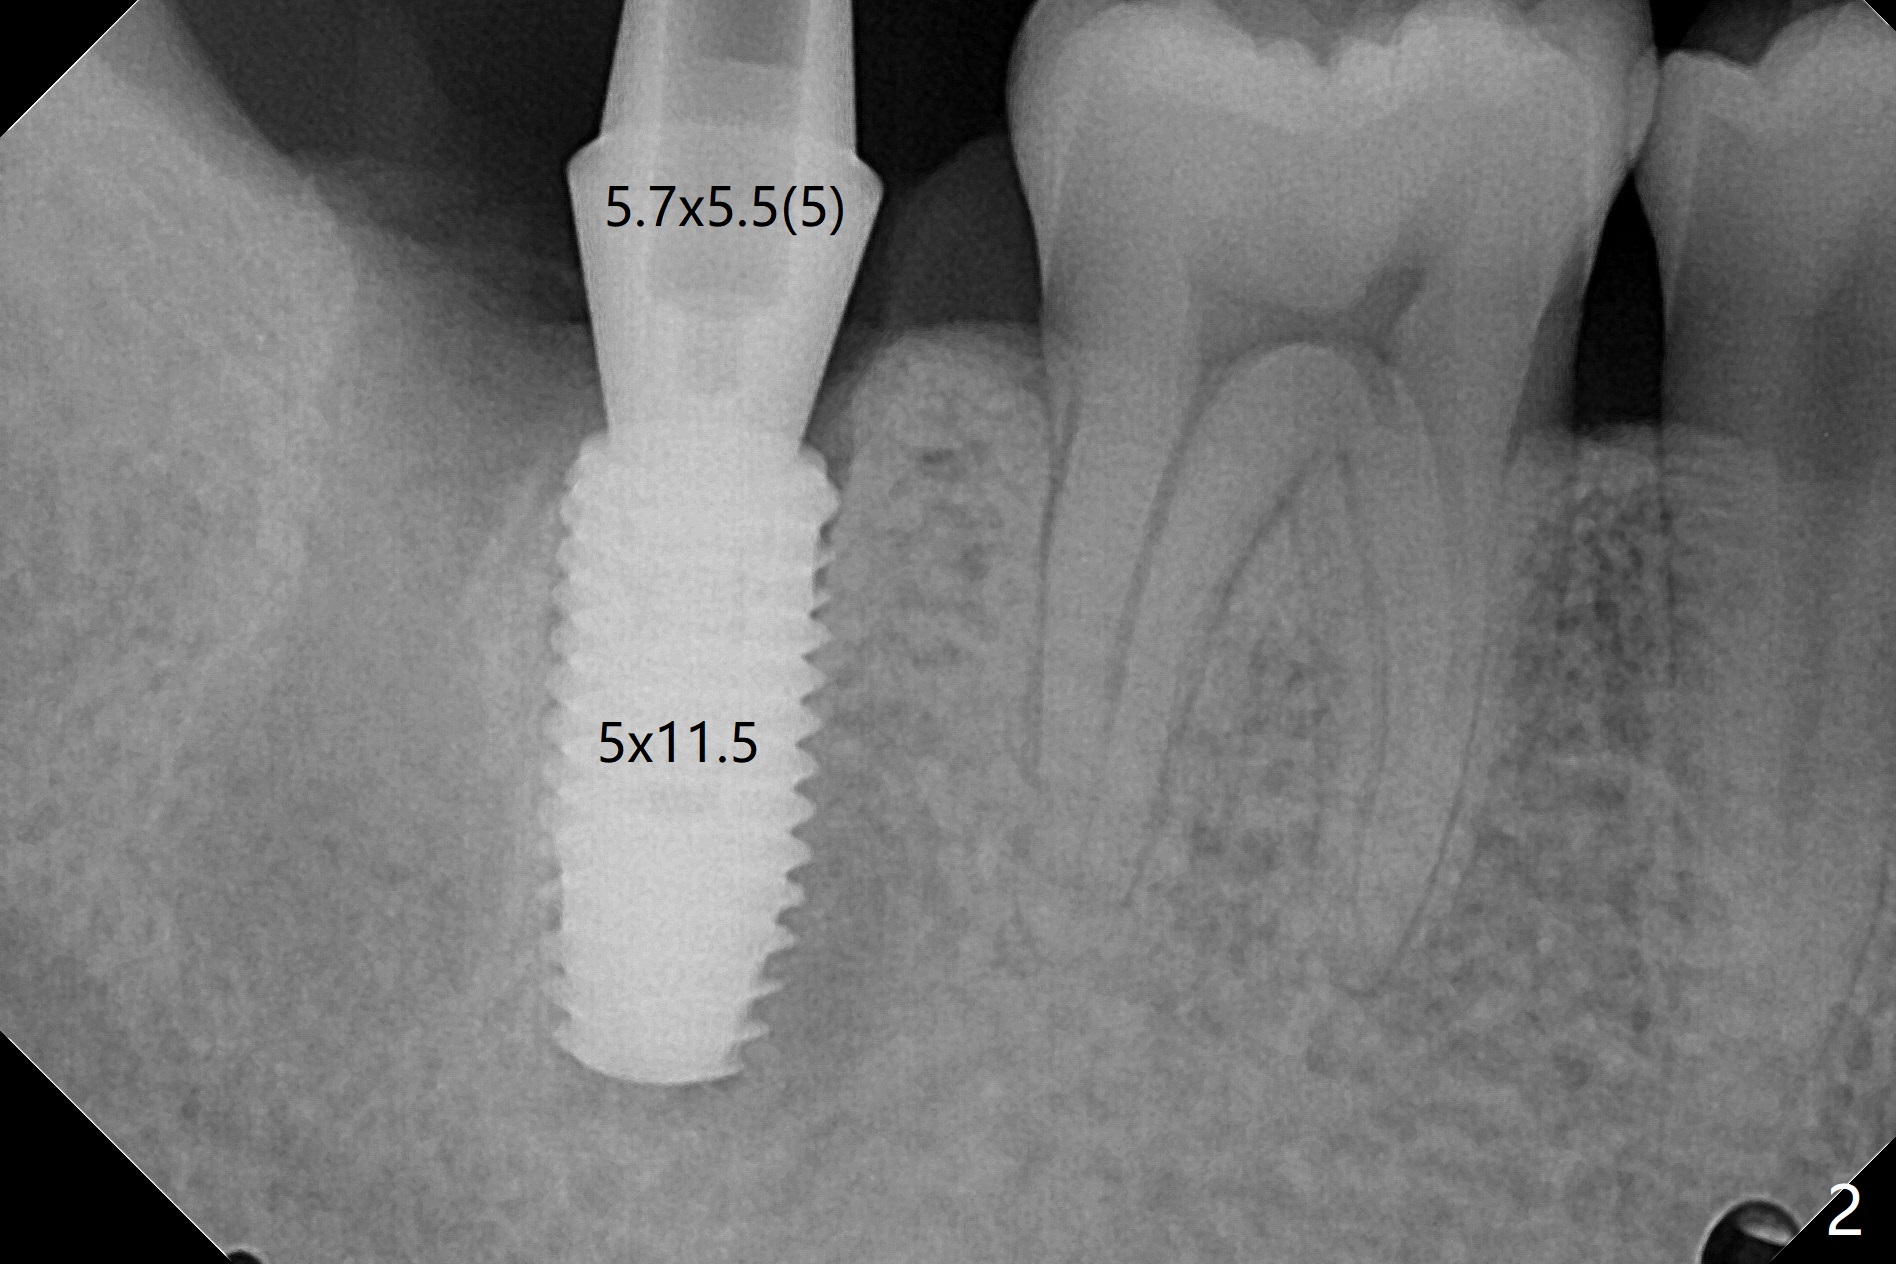

考虑到31号牙严重骨质吸收尤其是远中窝根尖(图一:*),实验室建议钻洞直径要比植体小三号(3.5毫米钻头;5.0毫米植体),其实行不通,使用4.0毫米钻头后,勉强植入4.5毫米报废植体(图一),阴差阳错:植体进入近中牙槽窝,植体四周都有骨壁包绕,包括远中:中隔(S)。最后为了使用5x11.5毫米植体,必须用4.5毫米钻头和5毫米皮质骨攻螺纹(到第三格,多3毫米,图二);放置基台好像没有就位。使用6毫米profile drill(好像去除舌侧中隔)后,手感基台就位,但是根尖片显示(图三)与图二没有区别(植体太粗,看不清楚植体与基台接触)。放置粘性骨粉后(图四),制作临时牙冠,放置PRF后,衬里多次增加固定和与牙龈密合度。术后医嘱包括手术区不使用水牙线。术后一周复诊询问骨粉游出问题。如果第二下磨牙种植能够进入近中窝,不必使用导板,4.5毫米足够,X光片观察基台就位也容易。术后三个月骨粉好像转变成正常骨质(图五,六, 30 Ncm)。